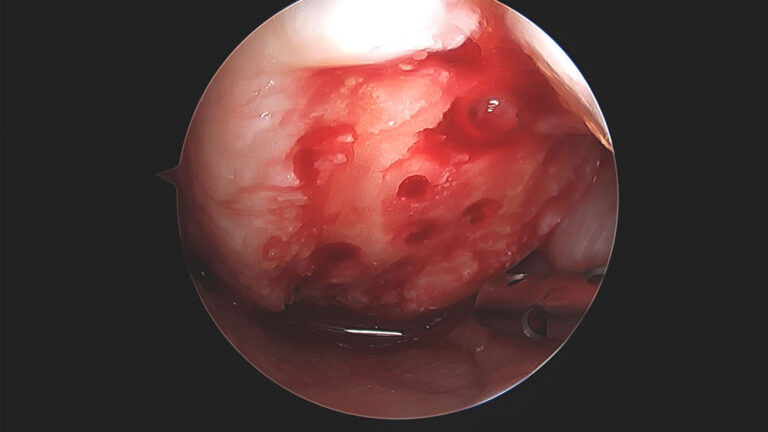

Chondral repairs assessed after 12 months revealed that nanofracture provided better healing at the footprint over microfracture, with better cartilage architecture and greater type II collagen content achieved.1

Compared to traditional microfracture and k-wire procedures, NanoFx showed superior bone marrow access with multiple trabecular access channels extending 9mm into subchondral bone.5

A Level I randomized controlled trial demonstrated that adding NanoFx nanofractures to the footprint during isolated supraspinatus tendon repair significantly improved healing outcomes.2 At 12-month follow-up, the re-tear rate was reduced by 50% compared to standard repair (19.4% vs. 42.4%, p = 0.038), with 94.4% of tendons successfully healed to bone in the NanoFx group versus 66.7% in controls (p = 0.014).1 This enhanced healing is attributed to deeper, more consistent marrow access and improved biological response at the tendon-bone interface.2